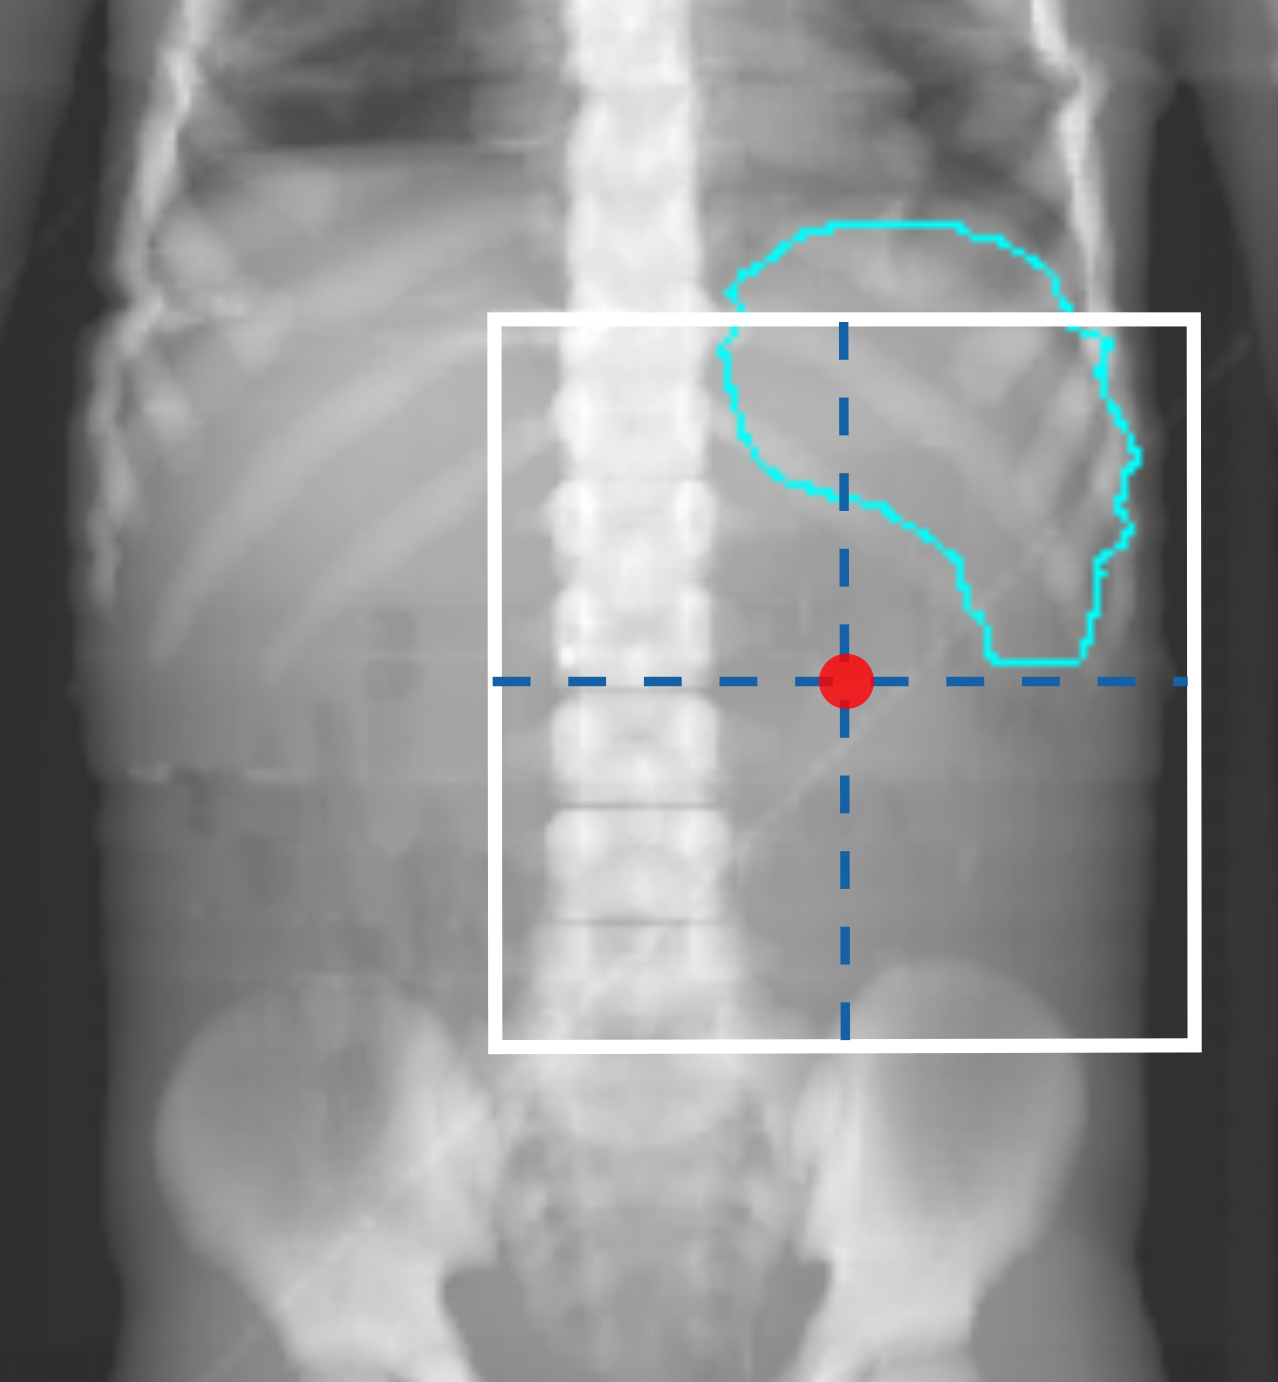

Figures 1(a) and 1(c) illustrate examples of actual historical plans on respective historical radiographs. As can be observed, a typical historical flank irradiation field is a rectangular area, with possible shielding blocks, that is located on the right or on the left flank. Irradiation is done by beams from anterior-posterior (AP) and posterior-anterior (PA) direction. Along right-left (RL), one field border is located at the edge of the patient’s body contour, while the other is located as to include the vertebral column (?). In some cases, blocks are placed to protect OARs from irradiation (Fig. 1(c)). In historical plans the isocenter is positioned in the center of the treatment field that is projected on the coronal plane (Fig. 1) and at the middle of the patient’s AP abdominal diameter.

To generate artificial plans, two reference digitally reconstructed radiographs (DRRs) were considered, randomly selected from the data. One DRR was derived from a CT of a 5-year old female patient without nephrectomy (ref 1 in Fig. 2), and the other was derived from a CT of a 4-year old female patient with nephrectomy of the left kidney (ref 2 in Fig. 2). Upon these two DRRs, boundaries defining the extent of variation for clinically reasonable fields were identified by an experienced pediatric radiation oncologist (B. V. Balgobind) Note that historical clinical guidelines are slightly different from current ones (e.g., currently the iliac crests should be safeguarded, unlike in Fig. 1(c)). Figure 2 shows two examples of landmark locations identifying possible plan variations, on the two reference DRRs. Specifically, given the boundaries of possible isocenter positions and field borders, plans with a rectangular field were generated by sampling uniformly within those boundaries.

For each plan generated, an additional version of that plan including one block was generated as well. A block was simulated as the area in the upper lateral corner enclosed by the border of the rectangular field and a line crossing two randomly sampled endpoints. The endpoints were sampled from two regions roughly covering the start and end points of rib 9 and rib 12 on the DRRs (regions indicated by the green boxes in Fig. 2). This way, a sampled block covered part of the liver (in right-sided plans) or part of the spleen (in left-sided plans). All plans consisted of two opposing and symmetrical beams in AP-PA directions irradiating one side of the abdominal flank. Figures 1(b) and 1(d) illustrate two examples of sampled artificial plans (without or with a block) on respective DRRs.